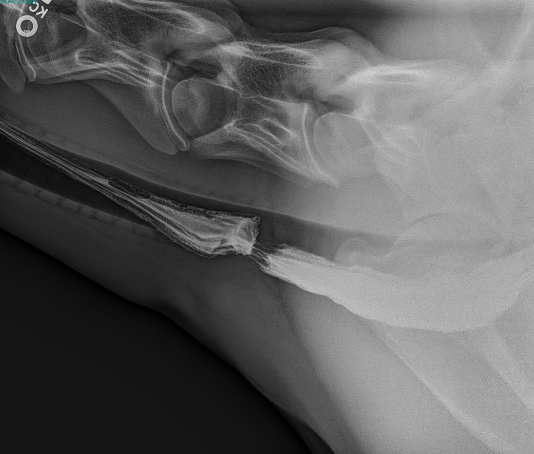

how are radiographs helpful for diagnosing choke in horses?

can help identify:

-location and length of obstruction

-evidence of esophageal rupture

-esophageal abnormalities (diverticulum, megaesophagus, stricture)

-assess lungs